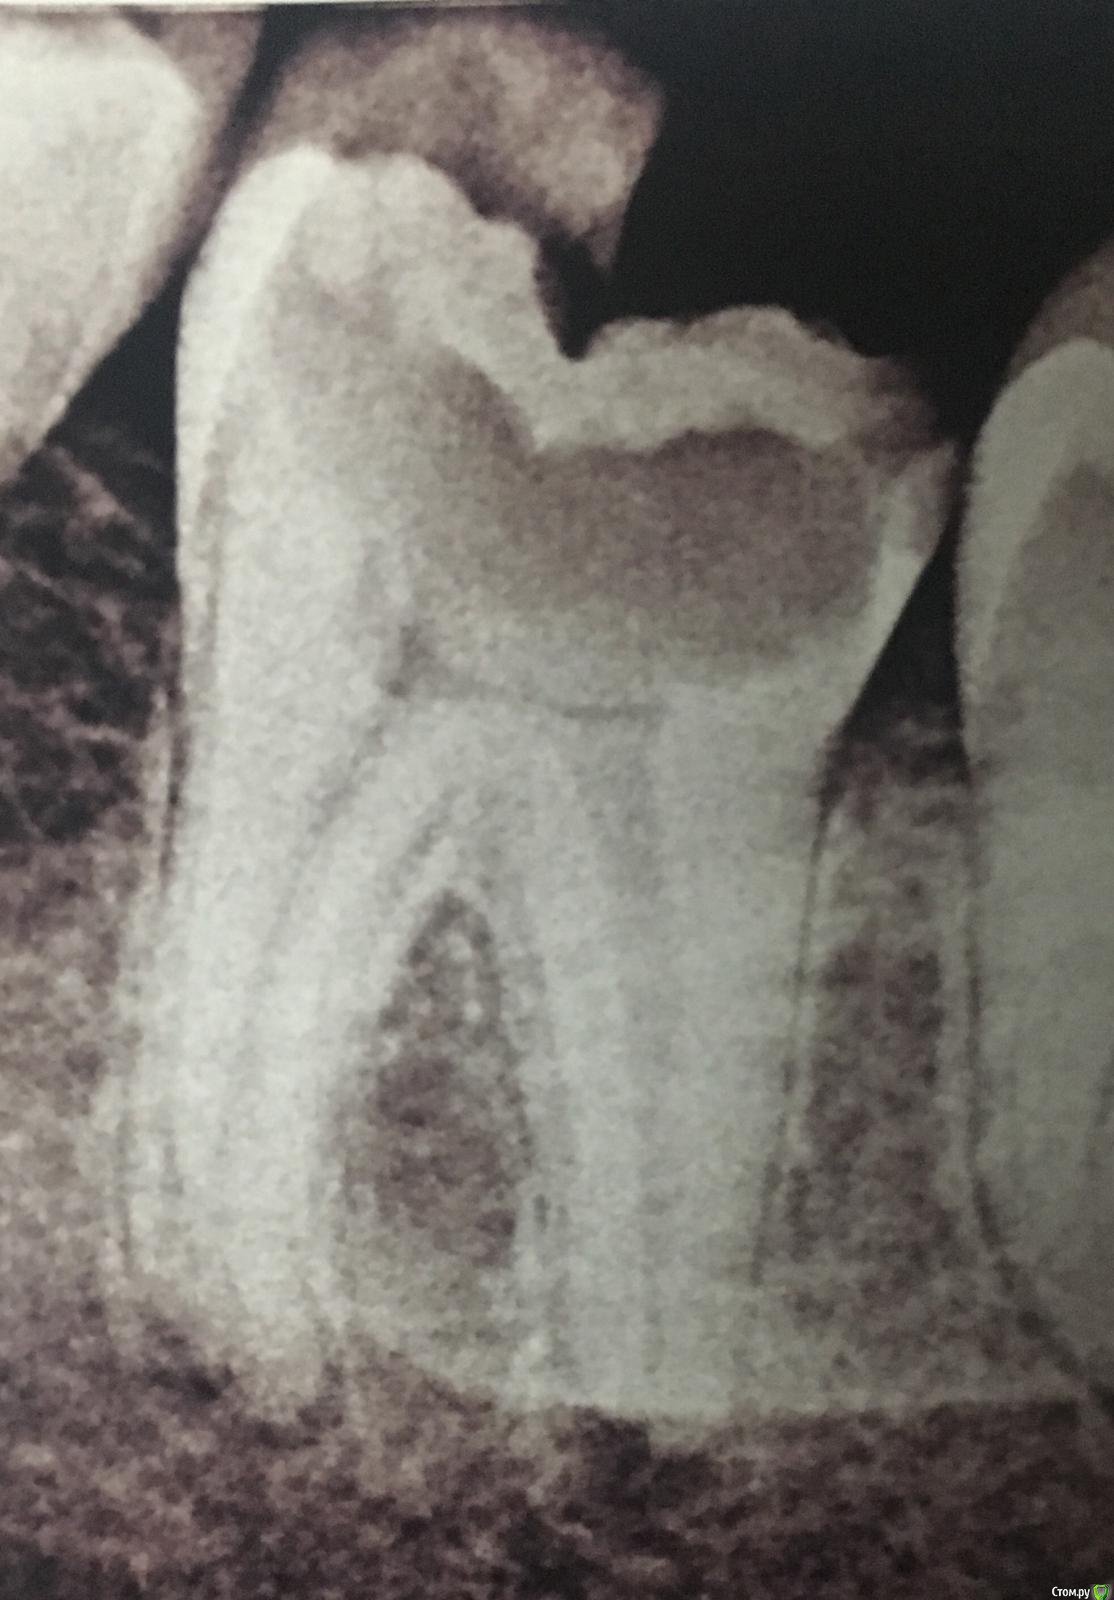

muemag Опубликовано 5 декабря, 2018 Поделиться Опубликовано 5 декабря, 2018 Около полугода назад откололась четверть 37 зуба, с недавнего времени начал беспокоить после еды.Вопрос в следующем, можно ли его спасти либо это "мертвому припарка"?Штифты коронки И так далее не интересуют, если и да то только полный имплант.И возможно ли стянуть вместе 8 и 6 ближе друг к другу если все таки удалят. Ссылка на комментарий

AndyAndy Опубликовано 5 декабря, 2018 Поделиться Опубликовано 5 декабря, 2018 Вы спрашиваете, можно ли его спасти, при этом вас не интересует штифт и коронка. А спасти его, думаю, возможно, но с помощью «штифта/вкладки и коронки». И только после оценки состояния твёрдых тканей (после препарирования кариеса)Судя по тому, что полгода вы уже ходите с такой полостью в зубе... наверное вы его спасать не намерены) 2 Ссылка на комментарий

Neilrus Опубликовано 5 декабря, 2018 Поделиться Опубликовано 5 декабря, 2018 зуб лучше чем имплантат, даже если на 5-8 лет. И да, надо снять все плохое и посмотреть сколько хорошего останется. Если не удаление зуба, то однозначно "лечение каналов" вас ждет...а там коронки, вкладки, штифты..как бог пошлет Ссылка на комментарий